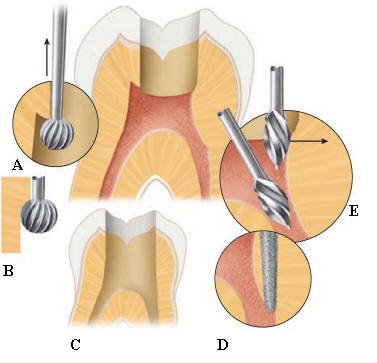

Fresas de

Gates Glidden

El

ensanchador Gates Glidden tiene un extremo

cortante corto, en forma de llama, con hojas

cortantes laterales levemente espiraladas

con ángulo muy inclinado respecto de la

vertical. Generalmente tiene una pequeña

guía no cortante en su extremo para

minimizar su potencial de perforación de la

superficie radicular. Ver imagen

izquierda

La cabeza

cortante está conectada al vástago por un

fino y largo cuello. Está numerado del 1 al

6 mediante marcas en el tallo del

instrumento. Se utilizan para la ampliación

y conformación de los conductos después del

limado seriado y ensanchamiento con limas,

en sus tercios cervical y a veces hasta el

tercio medio. Ver imagen derecha

Los taladros

Gates Glidden están diseñados con un punto

débil en la parte del eje más cercana a la

pieza de mano, de forma tal que el

instrumento fracturado pueda ser retirado

fácilmente del conducto. Se fabrican de acero

inoxidable y con un largo desde la punta hasta el

contrángulo de 18 mm.